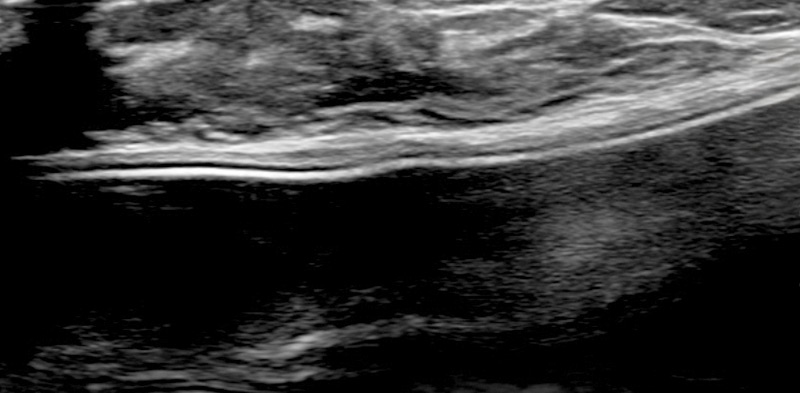

보형물 가슴성형 후 제법 크기가 있는 종양이 발견된 사례입니다.

가슴성형 후 맘모톰시술은 보형물의 위치를 파악하면서 바늘을 다루어야 하기 때문에 고도의 숙련도와 정밀한 판독 능력이 필요합니다.

한송이 원장은 다양한 사례를 접해온 경험과 전문성을 바탕으로 시술을 성공적으로 마쳤습니다.

총조직검사 후 최종 진단 결과 양성 종양(섬유선종)으로 확인되어 맘모톰 시술로 제거를 진행했습니다. 7개월 경과 후 검사를 통해 인공 보형물의 누수 및 파손 없이 깨끗한 내부 상태가 확인되었습니다.